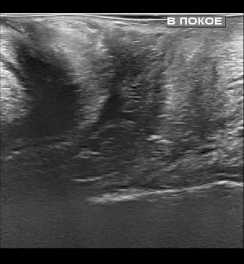

По результатам проведенных контрольных УЗ исследований нами было установлено, что при трансректальном исследовании толщина ректовагинальной перегородки увеличилась в среднем с 1,1+/–0,2 см до 1,5+/–0,2 см. Перегородка со стороны прямой кишки обрела четкие контуры за счет уменьшения ее складчатости. Произошло уменьшение диастаза бульбокавернозных мышц с 0,9+/–0,2 см до 0,3+/–0,1 см. При трансперинеальном УЗИ уменьшилась толщина перегородки за счет снижения ее складчатости и регрессировал пролапс перегородки в сторону влагалища при натуживании пациенток (рис. 1).

До операции

После операции

До операции После операции

Рис. 1. УЗИ картина до и после операции

Fig. 1. Ultrasound picture before and after surgery